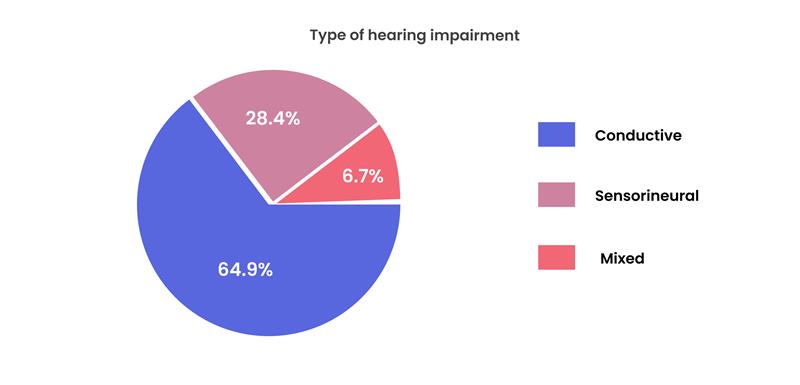

Risk Factors for Hearing Impairment Among Primary School Deaf Children in Gaza Strip, Palestine

Objective: This study was carried out to determine the risk factors associated with hearing impairment among primary school deaf children...Read More